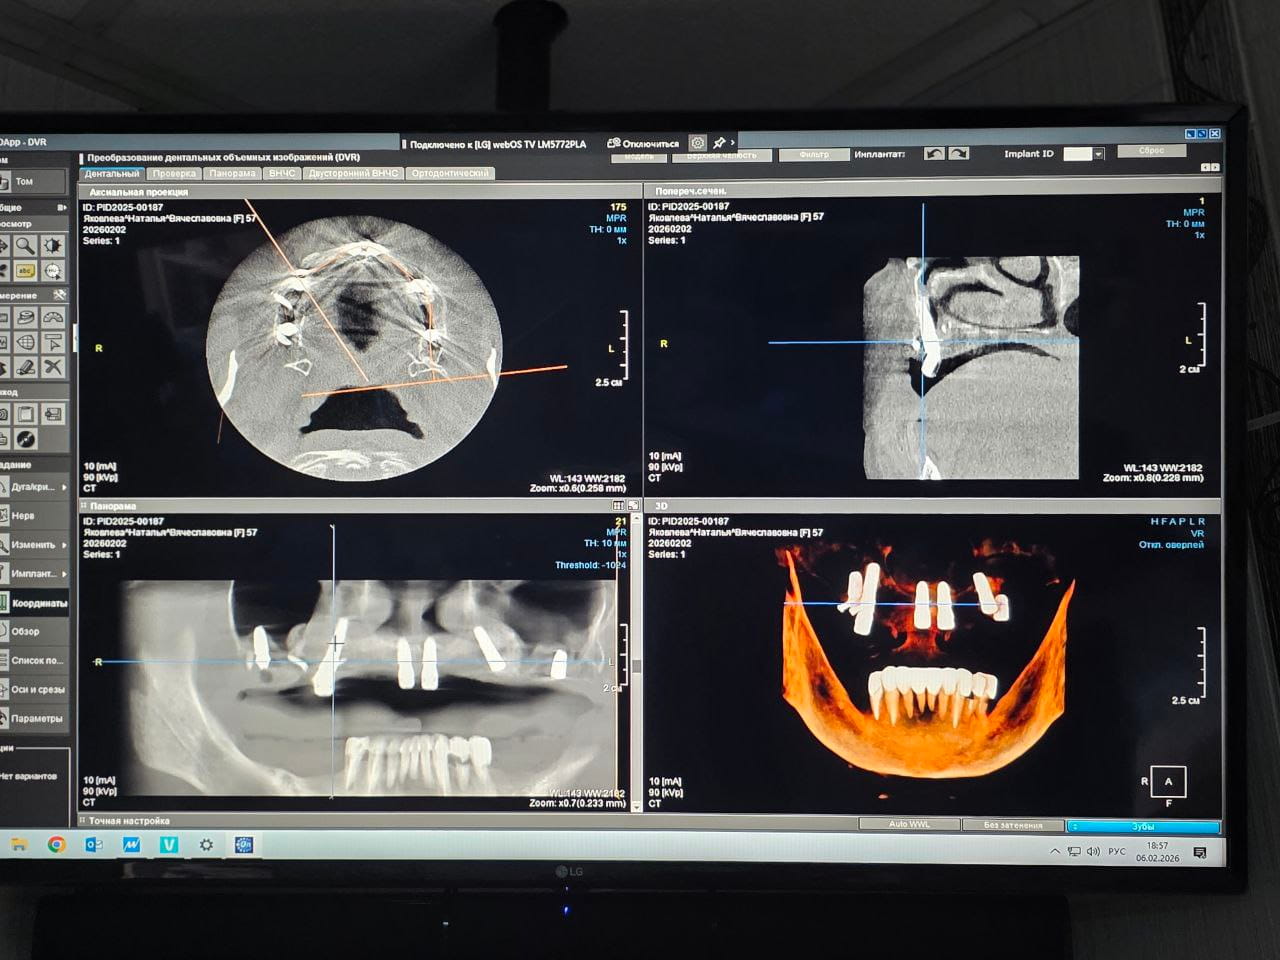

Компьютерная томография

Высокотехнологичный метод диагностики, использующий рентгеновское излучение и цифровую обработку изображений для получения трёхмерных реконструкций зубочелюстной системы.

Томограф создает детальные снимки внутренней структуры зубов, костей и прилегающих тканей, что позволяет выявить патологии, спланировать лечение и повысить точность проводимой терапии.